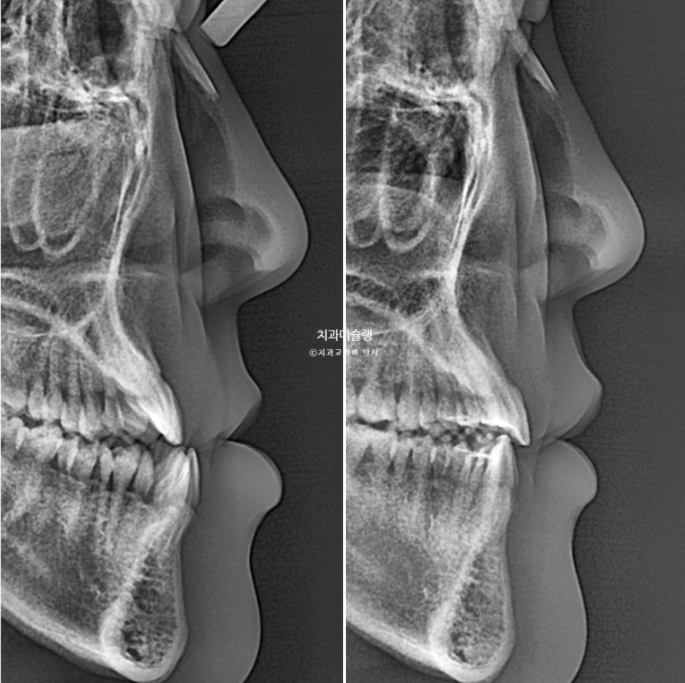

골격분석결과 양악수술이 필요한 상황이지만 환자분은 양악수술을 원치 않으셨습니다.

교정만으로 턱이 들어갈 순 없으나 아랫입술은 들어갈 수 있습니다.

23.06~26.01

아랫입술이 들어가면서 턱라인이 예뻐졌습니다.

아래 앞니는 아래턱뼈 치조골 한계가 허용하는 극한까지 뒤로 들어갔습니다.

아래 어금니들은 가용한 사랑니 공간을 최대한 이용하며 뒤로 들어갔습니다.

2년 반동안 치근흡수도 없고 치근평행도는 좋습니다.